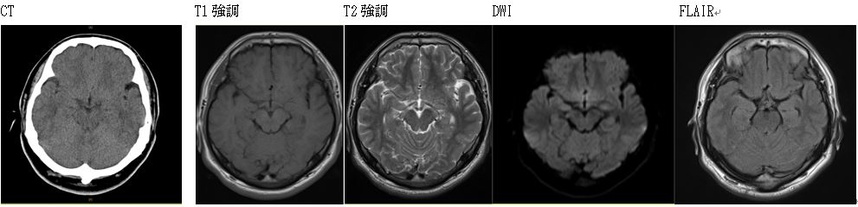

左くも膜下に淡い出血があると認められた画像(CT/MRIT1/T2/DWI/FLAIR)の比較

(乗用車同士の右直事故直進車同乗者・20代男性)

びまん性軸索損傷については、上記の平成30年報告のとおり、受傷当初のCT画像では特に異常が見つからず、MRI・T2*やFLAIR画像などで点状の微小出血痕として捉えられることがあります。

例えば、上記画像のとおり右側頭葉や小脳近縁部に点状出血痕がみられる場合、側頭葉が司る聴覚や言語理解力の低下が生じていないからといって、上記点状出血は高次脳機能障害を裏付ける画像所見でなない、とは必ずしも言えないのです。